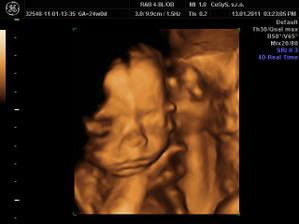

Naša lásočka 13+0tt...už teraz ju milujeme!)))